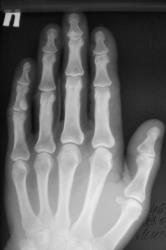

Катенёв Валенти... Дата публикации 19.06.2009, 20:43 Ваше мнение коллеги по поводу локального "уплотнения костной ткани" в средней фаланге 5 пальца левой кисти. Эностоз? Ваше мнение коллеги? Пт, 19/06/2009 - 20:46 #1 Глазков Игорь А... Не на сайте Был на сайте: 11 месяцев 3 недели назад Зарегистрирован: 19.12.2008 - 20:41 Публикации: 1597 что эностоз, но неплохо бы узнать возраст пациента. Прийди к Себе Пт, 19/06/2009 - 20:52 #2 Катенёв Валенти... Не на сайте Был на сайте: 7 лет 3 месяцев назад Зарегистрирован: 22.03.2008 - 22:15 Публикации: 54876 Пациент возраста около 30-ти лет.